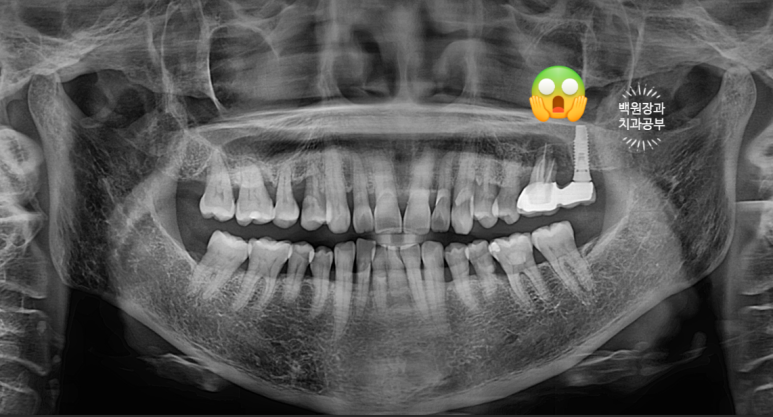

왠걸! 이런 보철물을 내가 직접 보게 되다니~

하나는 자연치아, 하나는 임플란트가 한 개의 보철물로 연결되어 있더라구요.

정확히 브릿지 (bridge)라고 부르지는 않지만, splinted crown 이라고 부릅니다.

교수님들 말씀이 맞았네요... 결국 자기 치아가 완전히 고장나버렸고,

주변은 염증이 가득 형성되서 잇몸뼈가 모두 사라져 버렸습니다.

너무 많이 뼈가 파괴되어 임플란트 심기가 어려워

추측컨데... 수술했던 임플란트 크라운이 너무 짧으니 잘 떨어질까봐 앞에 치아와 연결한게 아닐까 싶었습니다.

이번 환자분의 경우처럼 남은 뼈가 하나도 없는데 어떻게 심겠어요......

염증이 가득해 대부분의 뼈가 없어져서 상악동 하연과 잔존한 치조골 사이의 뼈가 대부분 사라져있는 그 때와 달리,